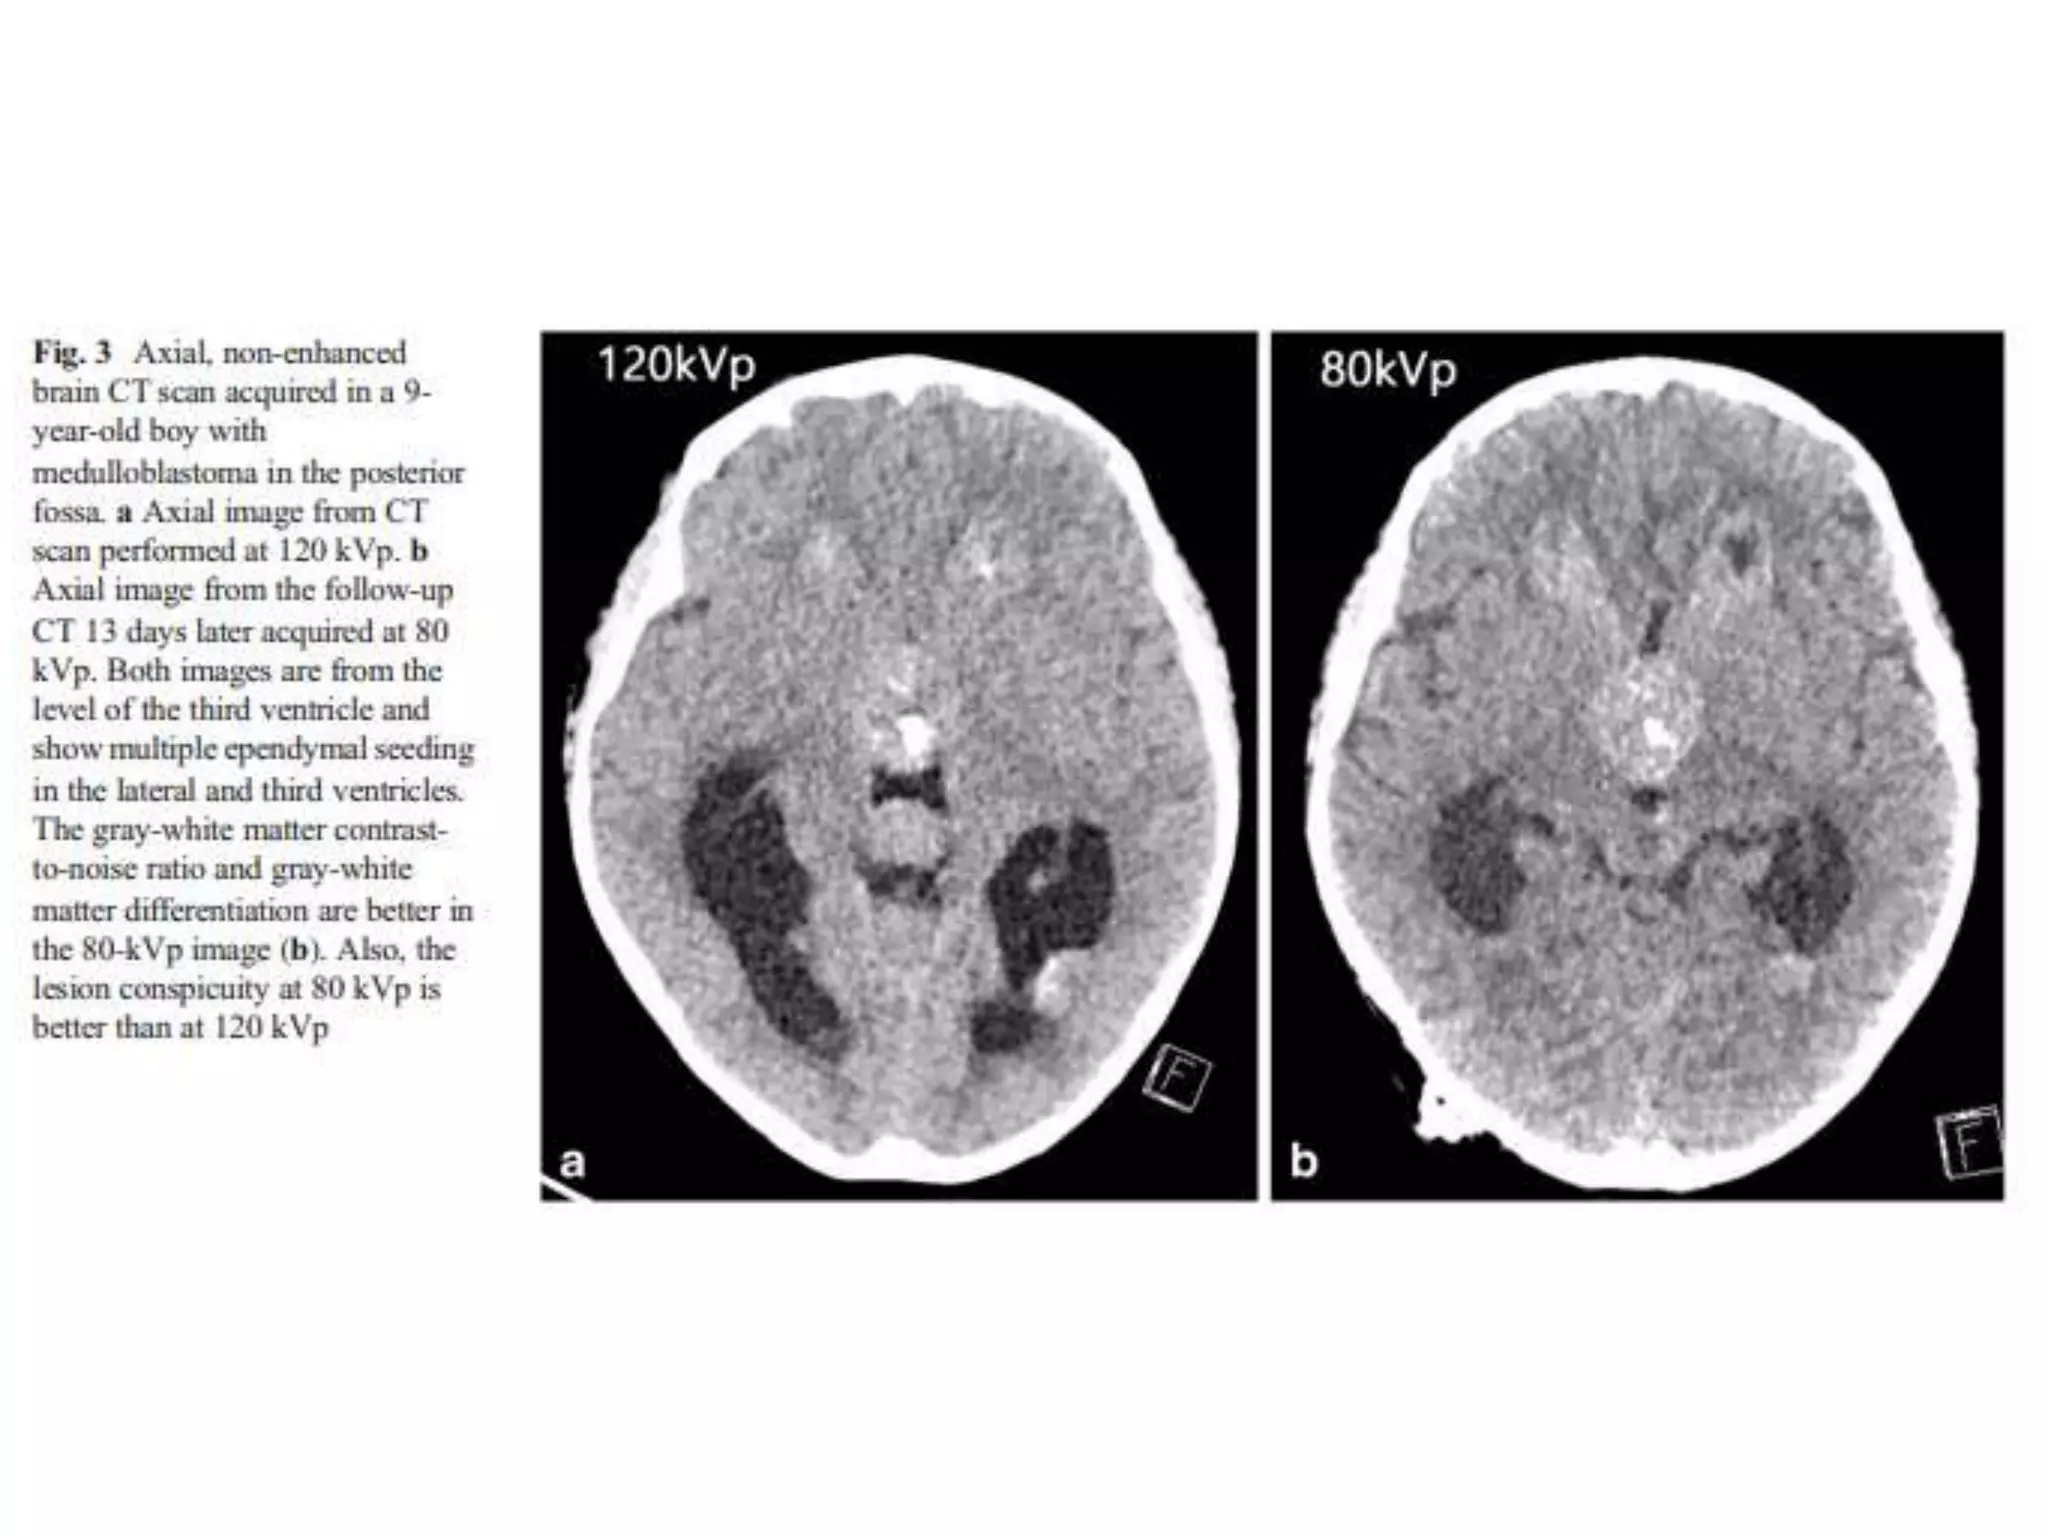

• 80 kV brain CT

– were shown to be with improved gray

matter-white matter contrast-to–noise ratios.

– Similar overall image quality

• 6.5% radiation dose reduction

• 80 kV brain CT can be an acceptable

technique to replace a standard 120 kV

CT scan in children

Conclusion • 80 kVbrain CT – were shown to be with improved gray matter-white matter contrast-to–noise ratios. – Similar overall image quality • 6.5% radiation dose reduction • 80 kV brain CT can be an acceptable technique to replace a standard 120 kV CT scan in children